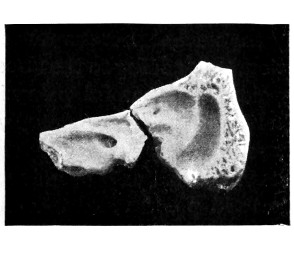

| 40 and 41. To show the relation of basic fractures to the petrous bone | 104, 105 |